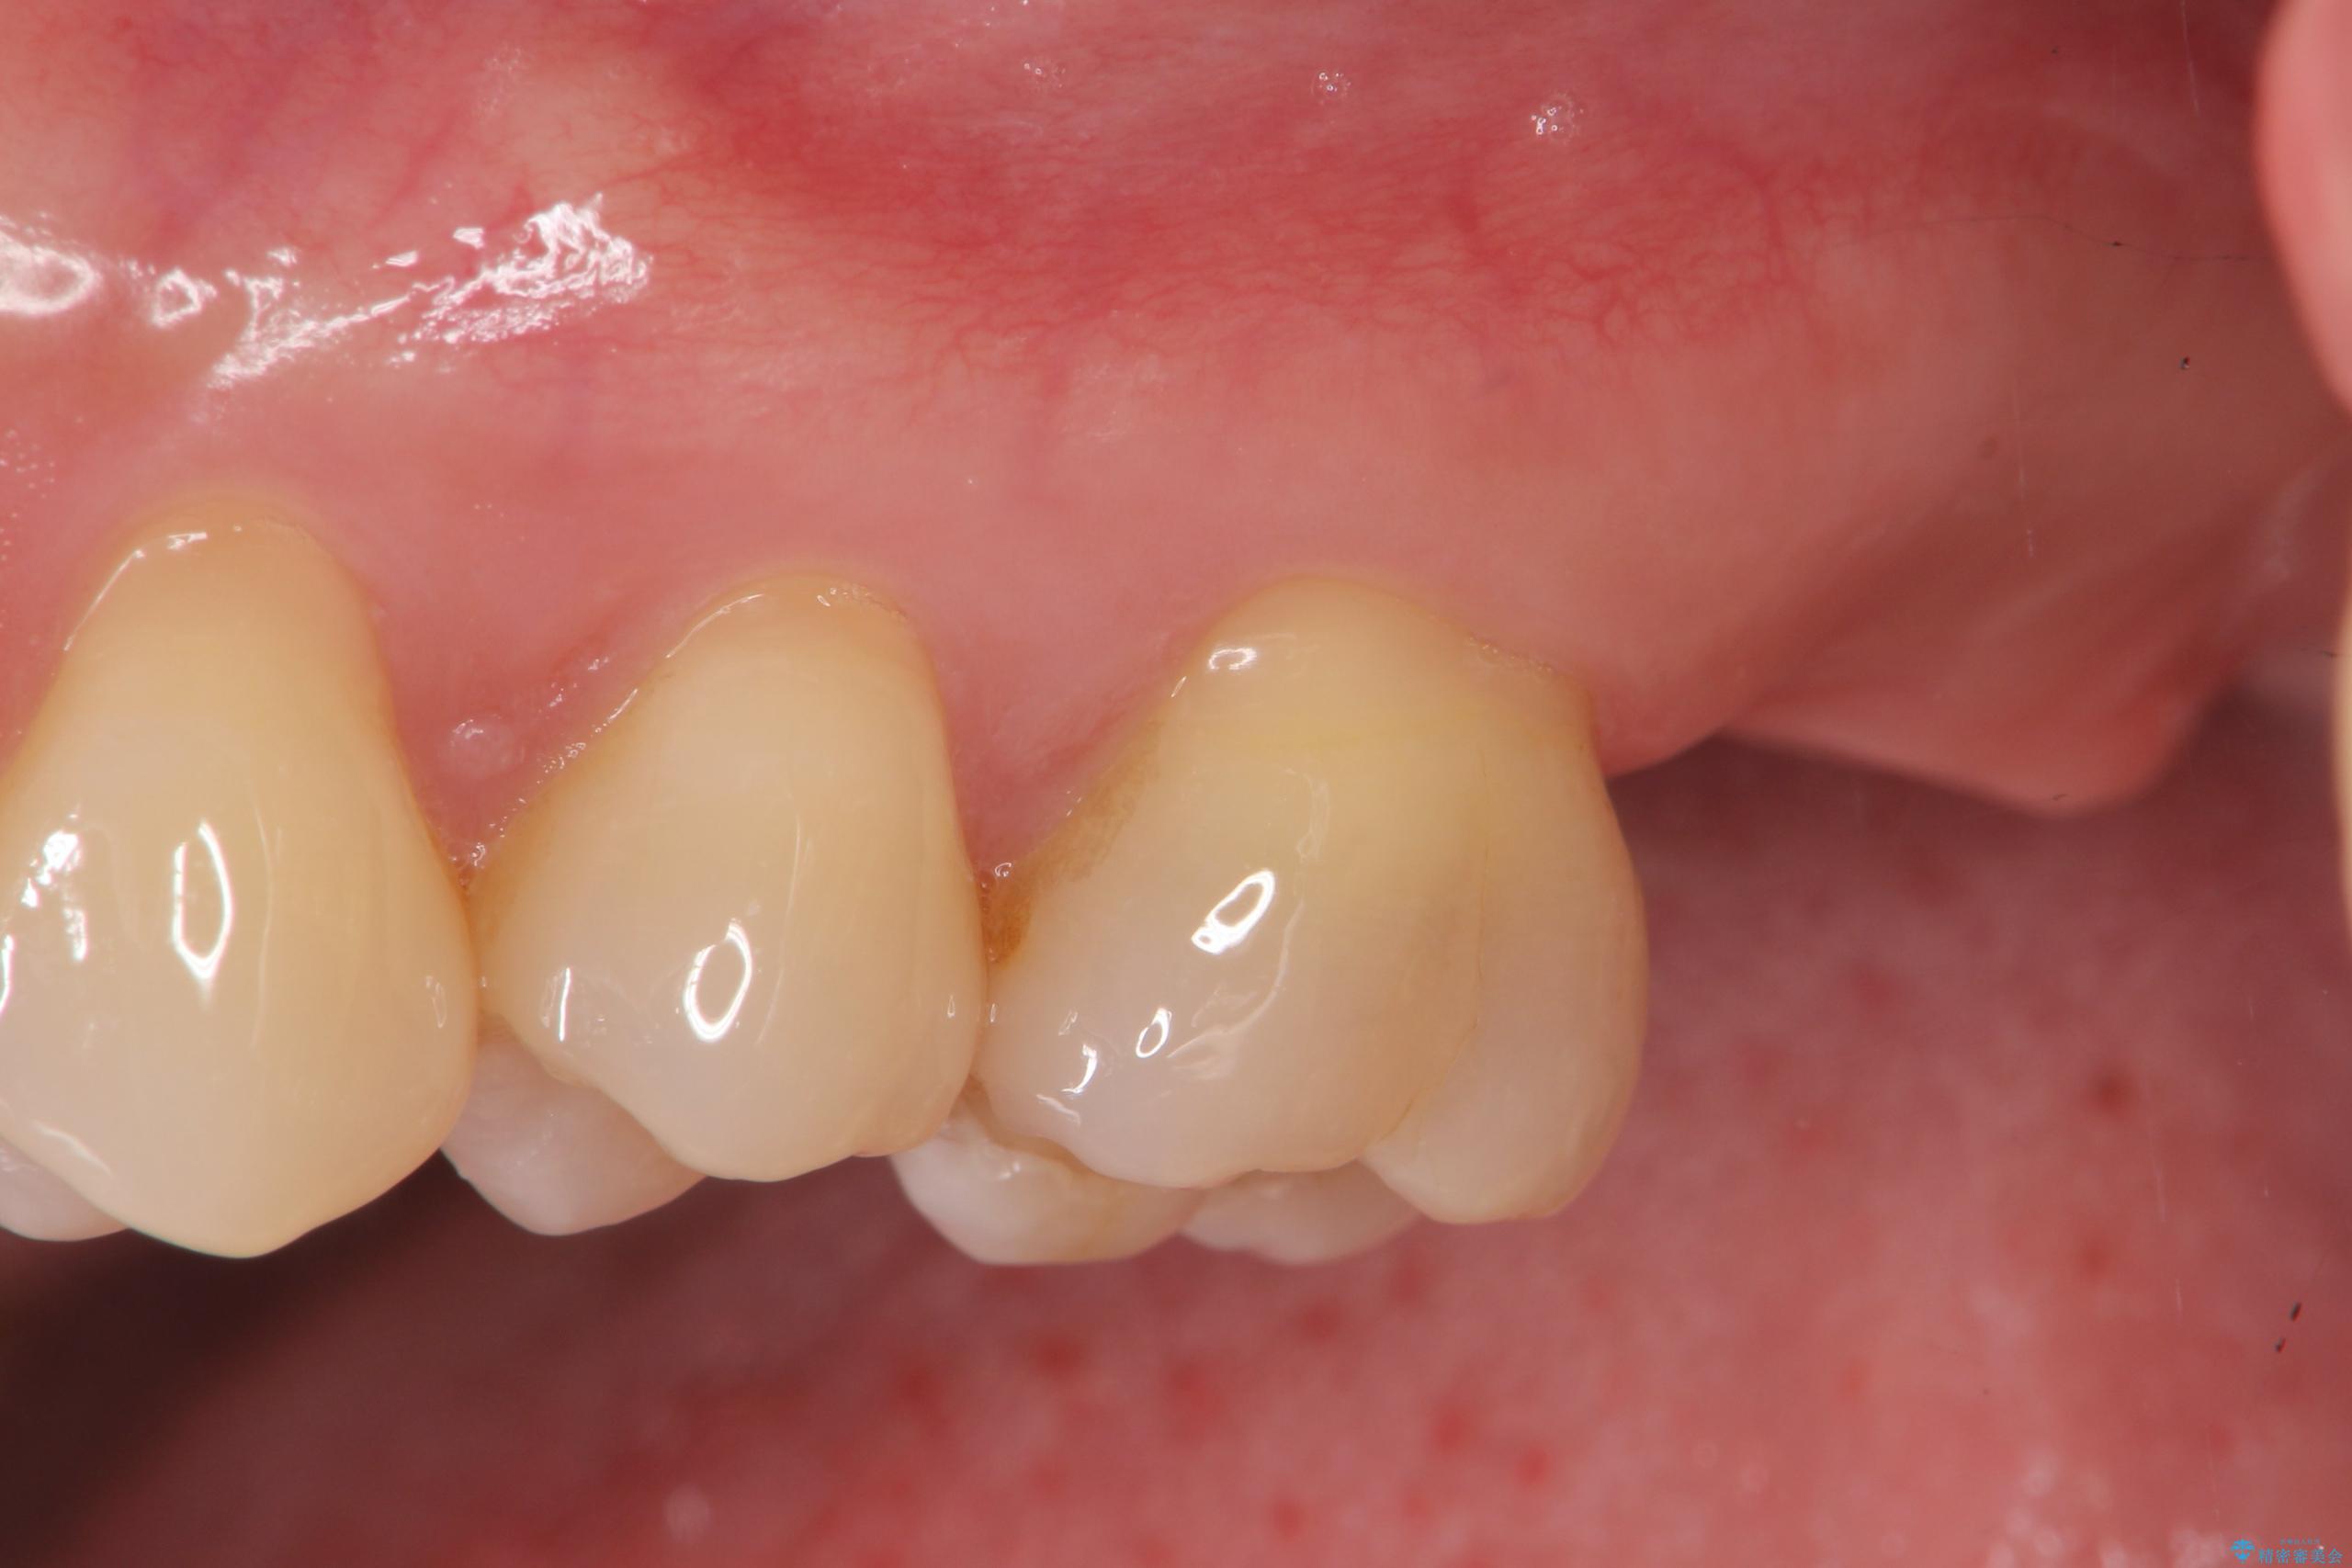

精査した結果、上顎奥歯は歯が割れてしまっており、根管治療ではなく抜歯の対象でした。

治療前

【噛むと歯が疼く】歯牙破折からのインプラント治療 治療前画像 【噛むと歯が疼く】歯牙破折からのインプラント治療 治療前画像 【噛むと歯が疼く】歯牙破折からのインプラント治療 治療前画像 【噛むと歯が疼く】歯牙破折からのインプラント治療 治療前画像 【噛むと歯が疼く】歯牙破折からのインプラント治療 治療前画像 【噛むと歯が疼く】歯牙破折からのインプラント治療 治療前画像 【噛むと歯が疼く】歯牙破折からのインプラント治療 治療前画像